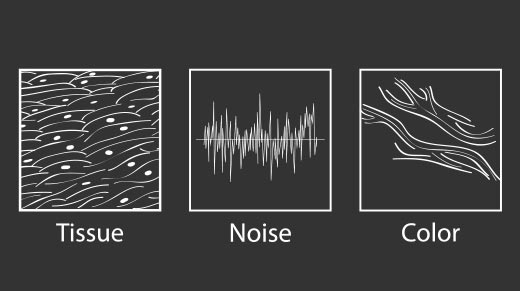

微米成像技术提升了对组织斑点噪声信号的抑制能力,并进一步强化边界信息,从而获得信噪比更优、边界更清晰锐利的图像。

通过对组织运动信息、血流信号及背景噪声进行准确阈值判定,高效提取出微弱血流信号,获得高灵敏度的空间分辨率的血流图像,为临床提供更加真实、丰富的诊断信息。